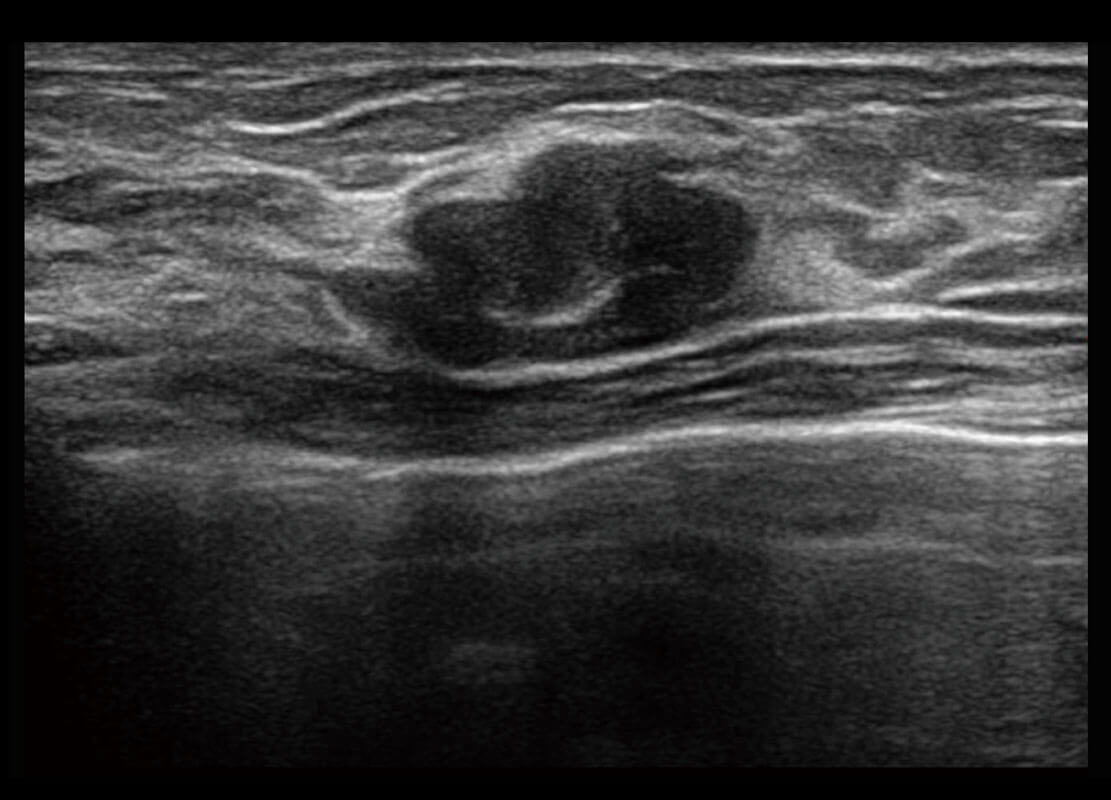

乳腺超声 / 新生儿

P60搭载宽频带线阵探头、宽景成像、弹性成像技术,为您提供乳腺全面应用方案。P60支持高频相控阵探头、线阵探头、腹部高频探头、腹部微凸探头等,丰富的探头群搭载敏感的彩色血流成像,适用于新生儿多种脏器检测要求,满足新生儿筛查需求。

• 乳腺导管癌

• 乳腺癌显微血流